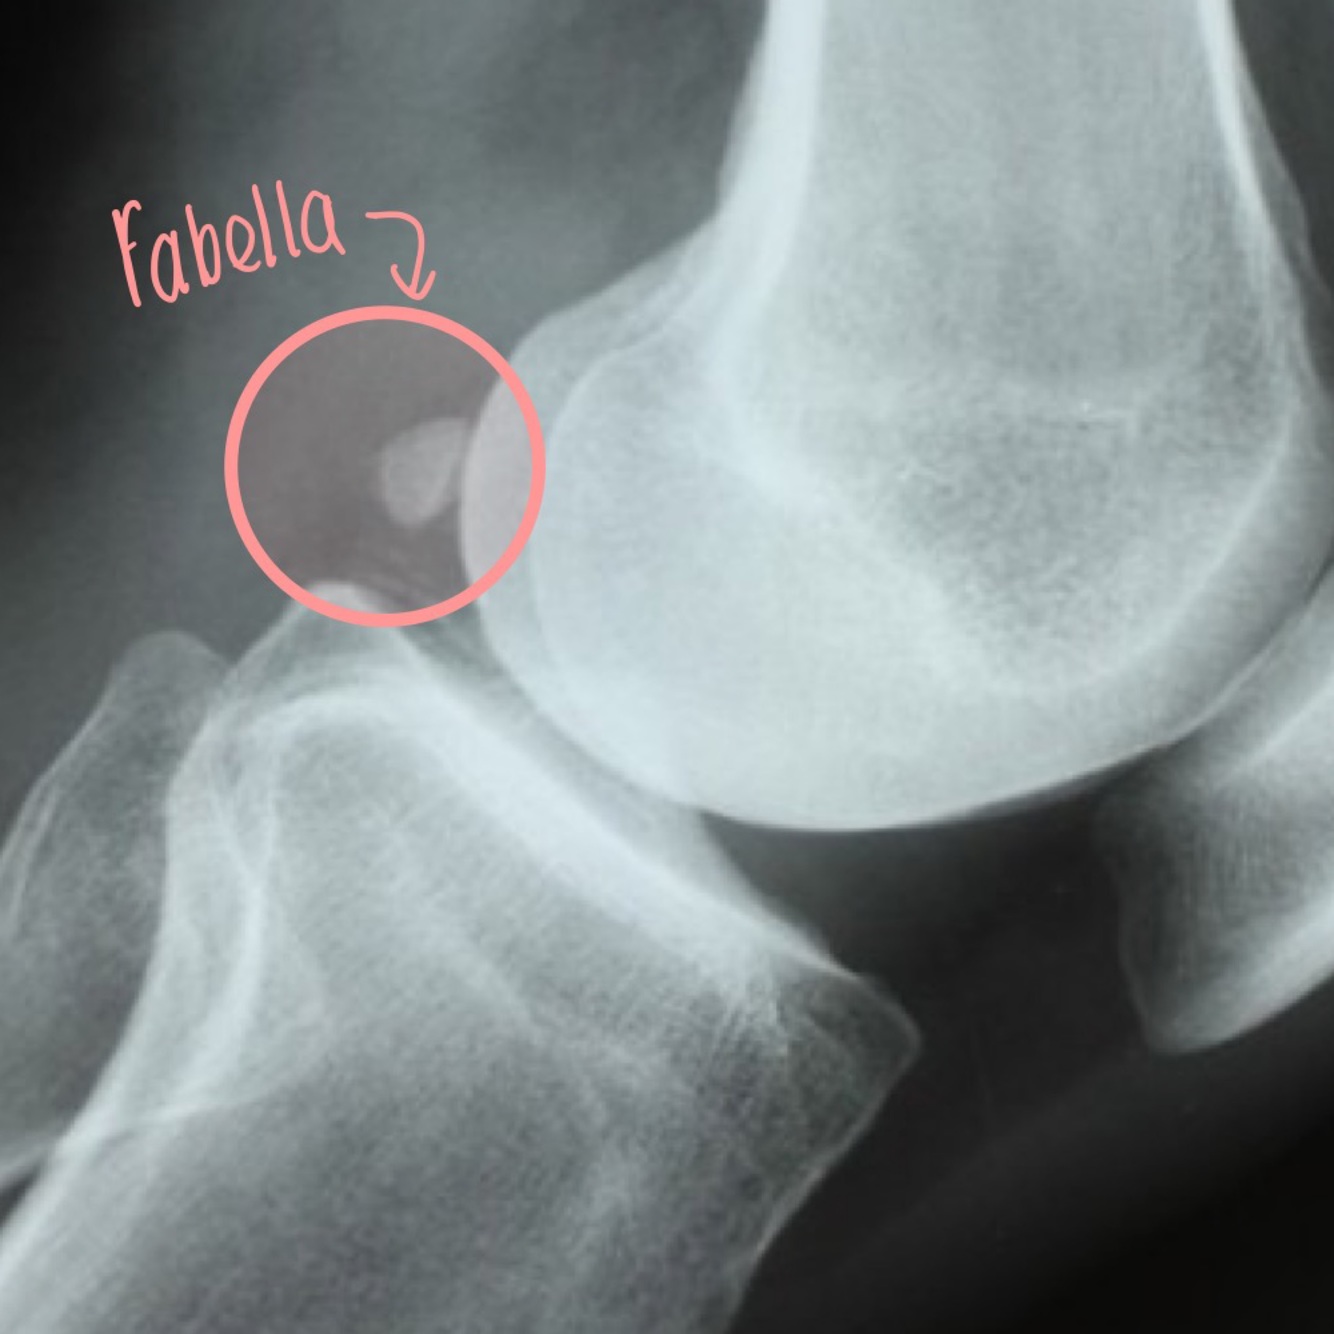

Qu’est-ce que je vois dans ma projection lat du genou

Genou fléchi entre 20 ̊-30 ̊

• Position de la rotule (baja, alta).

• Articulation fémoro-rotulienne de profil

• Attaches tendineuses du système extenseur

• Os fabella

• Évaluation de l’espace supra- patellaire à la recherche d’épanchement